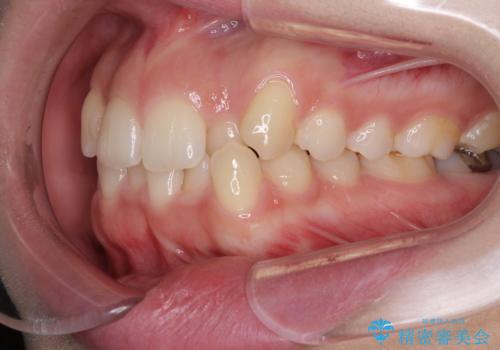

骨格的に左右にずれいている 前歯のデコボコをインビザラインで解消

- 前歯のデコボコと八重歯を気にして来院された患者様です。

叢生の程度は中等度であったため、IPR(歯と歯の間を削る)と歯列の側方拡大をメインに、インビザラインを用いて歯列を改善することとしました。

また、下顎骨の右側変位による右側臼歯の咬合を改善させるよう試みることとしました。

右側の咬合改善を目標に様々な手法を用いましたが、骨格的なズレによる不正咬合はインビザラインでは改善することができませんでした。